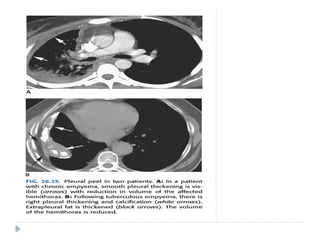

Pleural Thickening and

Fibrothorax

 Pleural thickening is common and is usually a sequel of

pleural inflammation.

 It may also be a delayed complication of hemothorax,

pleural empyema, and recurrent pneumothorax.

 Localized pleural thickening is frequently found at the

bases and results in blunting of the costophrenic angles

with tenting of the diaphragmatic pleura .

 Fibrous pleural thickening is also common in the apical

pleural cupola where it may be secondary to

tuberculosis or represent age-related change.

 These “apical pleural caps” sometimes have a scalloped

contour or may show slight tenting towards the lung

 Asbestos related diffuse pleural thickening is much less

common than discrete pleural plaques and involves the

visceral rather than the parietal pleura

 Evidence of underlying parenchymal disease is usually

seen in patients with prior tuberculosis or other

empyema.

 Hemorrhagic effusion, tuberculosis, and other causes of

empyema usually lead to unilateral pleural abnormalities

 benign asbestos pleurisy usually leads to bilateral pleural

 Involvement of the mediastinal pleura is more common

with mesothelioma or other malignancies .